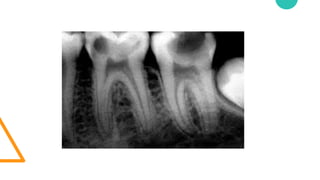

• El dentista mediante una exploración de la

zona y una radiografía determinará el

alcance del daño y decidirá el tratamiento

más adecuado.